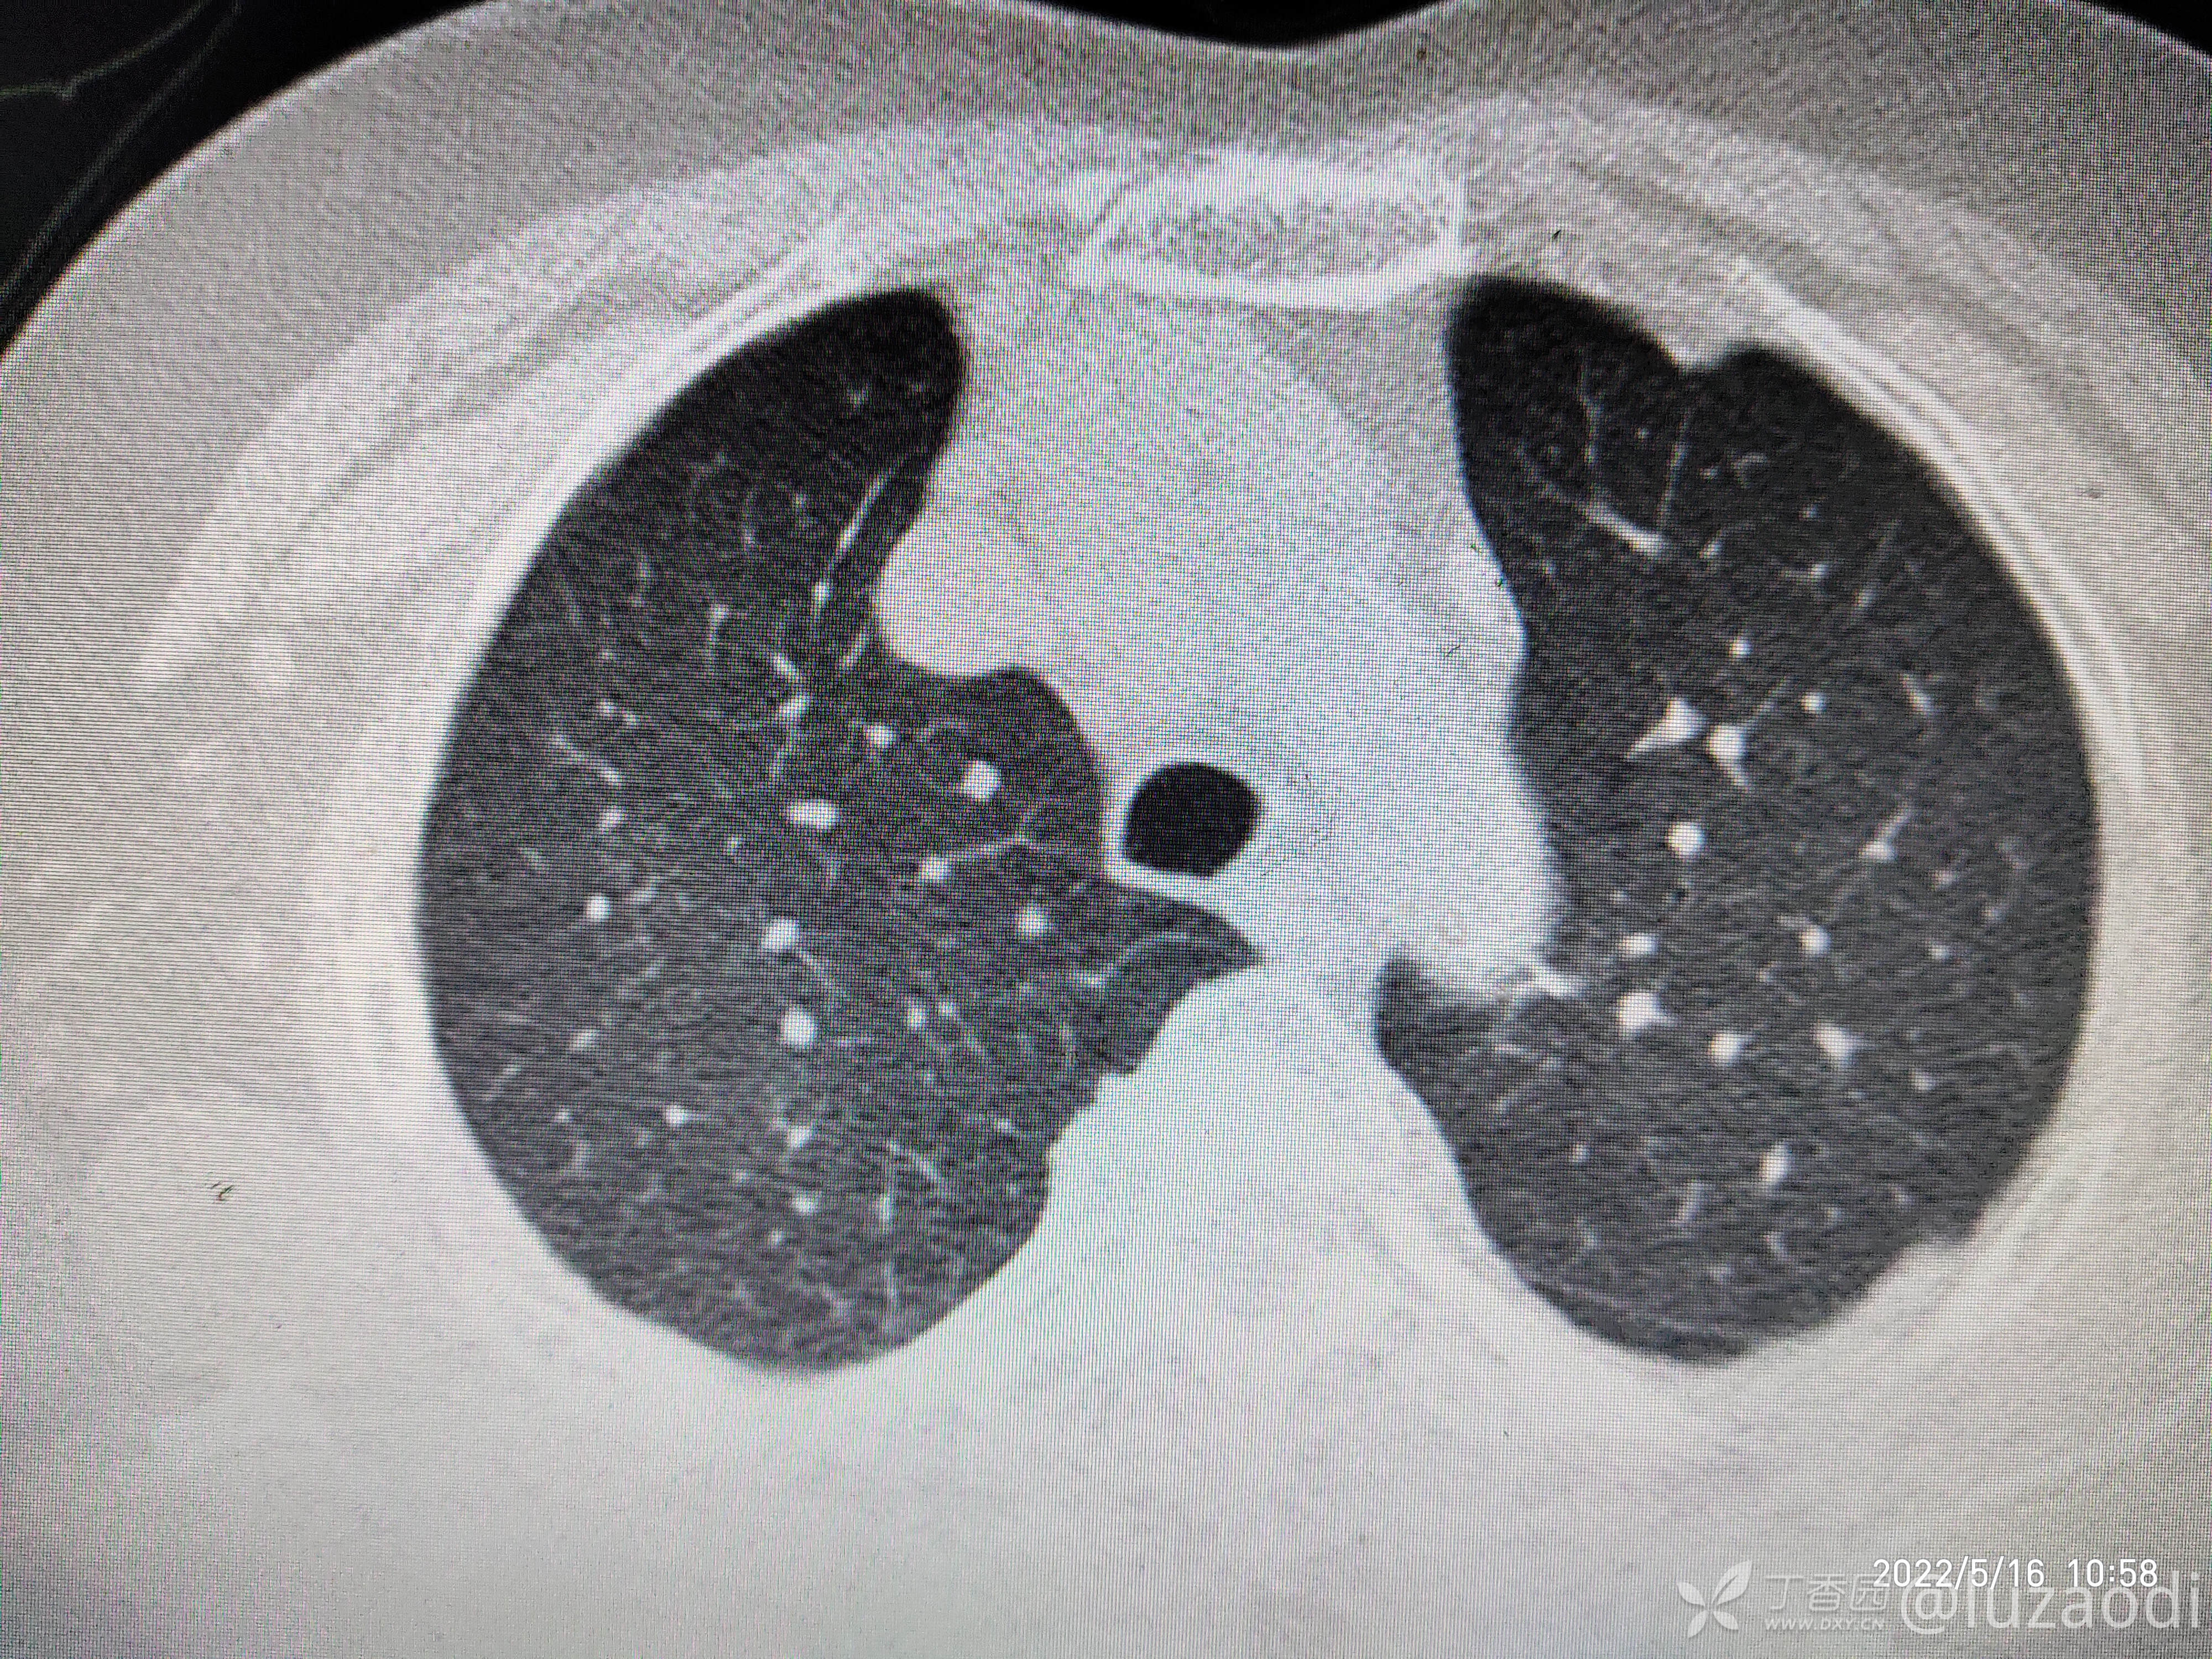

治疗经过:入院后患者仅有乏力,未见明显神经定位征。近期无发热、咳嗽、腹泻症状。遂予血糖、心电图、生化检查及影像检查,结果如下:

我去。。。。。视频只能上传一个,头颅CT上传不了,我直接说报告吧。头颅CT报腔隙性脑梗。